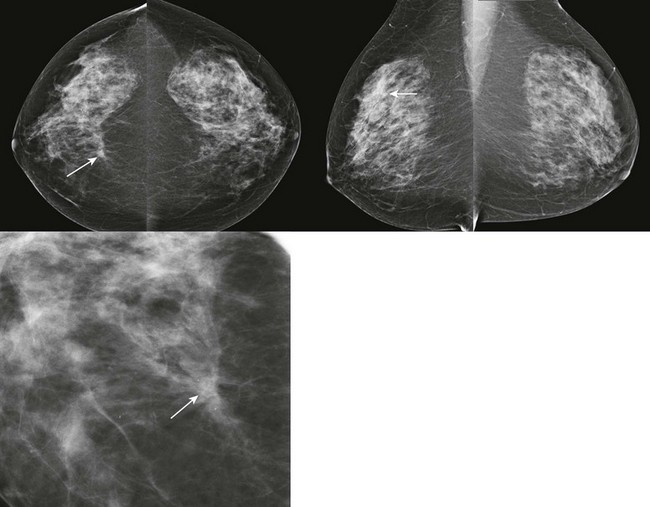

Radial scar can mimic ILC on mammography. Both frequently present as distortion without a central mass (the “dark star”). Radial scar is not actually a scar; it is not due to trauma or surgery, but does look somewhat like a scar at histologic examination. Benign lobules and ducts are entrapped by dense central fibrosis and elastosis, which results in the appearance of architectural distortion on the mammogram (Fig. 11-4). The cause is unclear, but these are proliferative lesions. Hyperplasia, atypical ductal hyperplasia, and papillomas are common in the surrounding tissue. From 10% to 30% of radial scars are associated with DCIS or IDC. Multiple small foci of carcinoma are not uncommon. A history of biopsy showing radial scar is also associated with a higher risk of breast cancer (relative risk of two times that of women without this history).

FIGURE 11-4 Radial Scar with Associated DCIS.

Architectural distortion is present in the right breast (circle). On US, there is a corresponding hypoechoic, irregular mass. Ultrasound-guided core biopsy showed radial scar. Excisional biopsy showed radial scar with associated DCIS.

Management of architectural distortion having the dark star appearance on mammography is somewhat controversial. Up to 29% of these women will have invasive carcinoma. At initial mammographic interpretation, either core biopsy or diagnostic surgical biopsy can be performed. Core biopsy showing a benign result will often result in a recommendation for excision of the area due the underlying distortion. On the other hand, surgeons may prefer to know before surgery if the pathologic finding is consistent with radial scar, requiring only a small volume excision, or invasive carcinoma, which requires a larger volume excision and nodal sampling. Hence, core biopsy can aid in biopsy planning (Box 11-3).

CASE 11-11. There is persistent architectural distortion without a central mass on mammography (“the dark star”). On US, there is an irregular hypoechoic mass with spiculated margins. The echogenicity of the mass on US is higher than that of most breast cancers, and there is no echogenic margin. The appearance on mammography and US suggests that this may represent a radial scar. ILC, IDC-NOS, or tubular carcinoma is also possible. The patient has no history of prior breast surgery, so this is not a surgical scar. Excisional biopsy showed radial scar/complex sclerosing lesion. Core biopsy often does not result in a diagnosis of radial scar because a larger sample is often needed to display the diagnostic morphologic appearance of this lesion. A benign result should be considered discordant, and likely to be a radial scar.